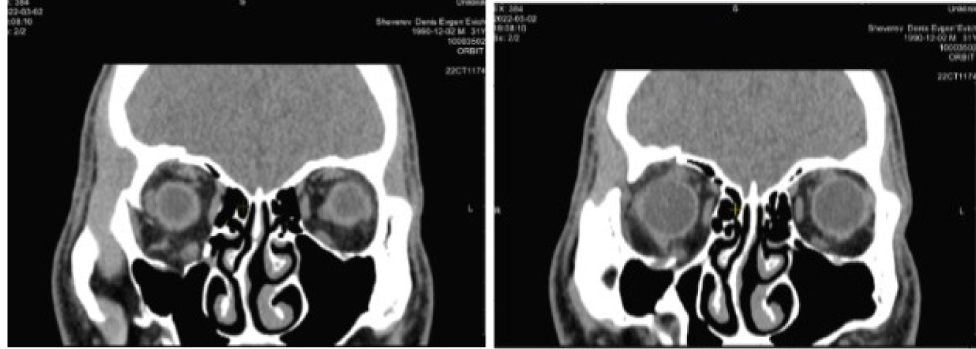

По результатам КТ и данным анамнеза на этапе планирования операции предположили отсутствие нижней прямой мышцы справа (рис. 6).

Пациентке поставлен диагноз: Оперированная травматическая деформация орбиты. Травматическое косоглазие. Рекомендовано хирургическое устранение косоглазия. С этой целью проведена нижняя парциальная транспозиция боковых прямых мышц в следующем объеме: от внутренней и наружной прямых мышц отделены порции в 2/5 ширины сухожилия, перемещены книзу и фиксированы в месте крепления нижней прямой мышцы. Также выполнена рецессия верхней прямой мышцы 3 мм. В раннем послеоперационном периоде отмечено уменьшение вертикальной девиации и появление подвижности книзу (рис. 7).

Рис. 6. Компьютерная томография орбит до операции. Клинический пример 2